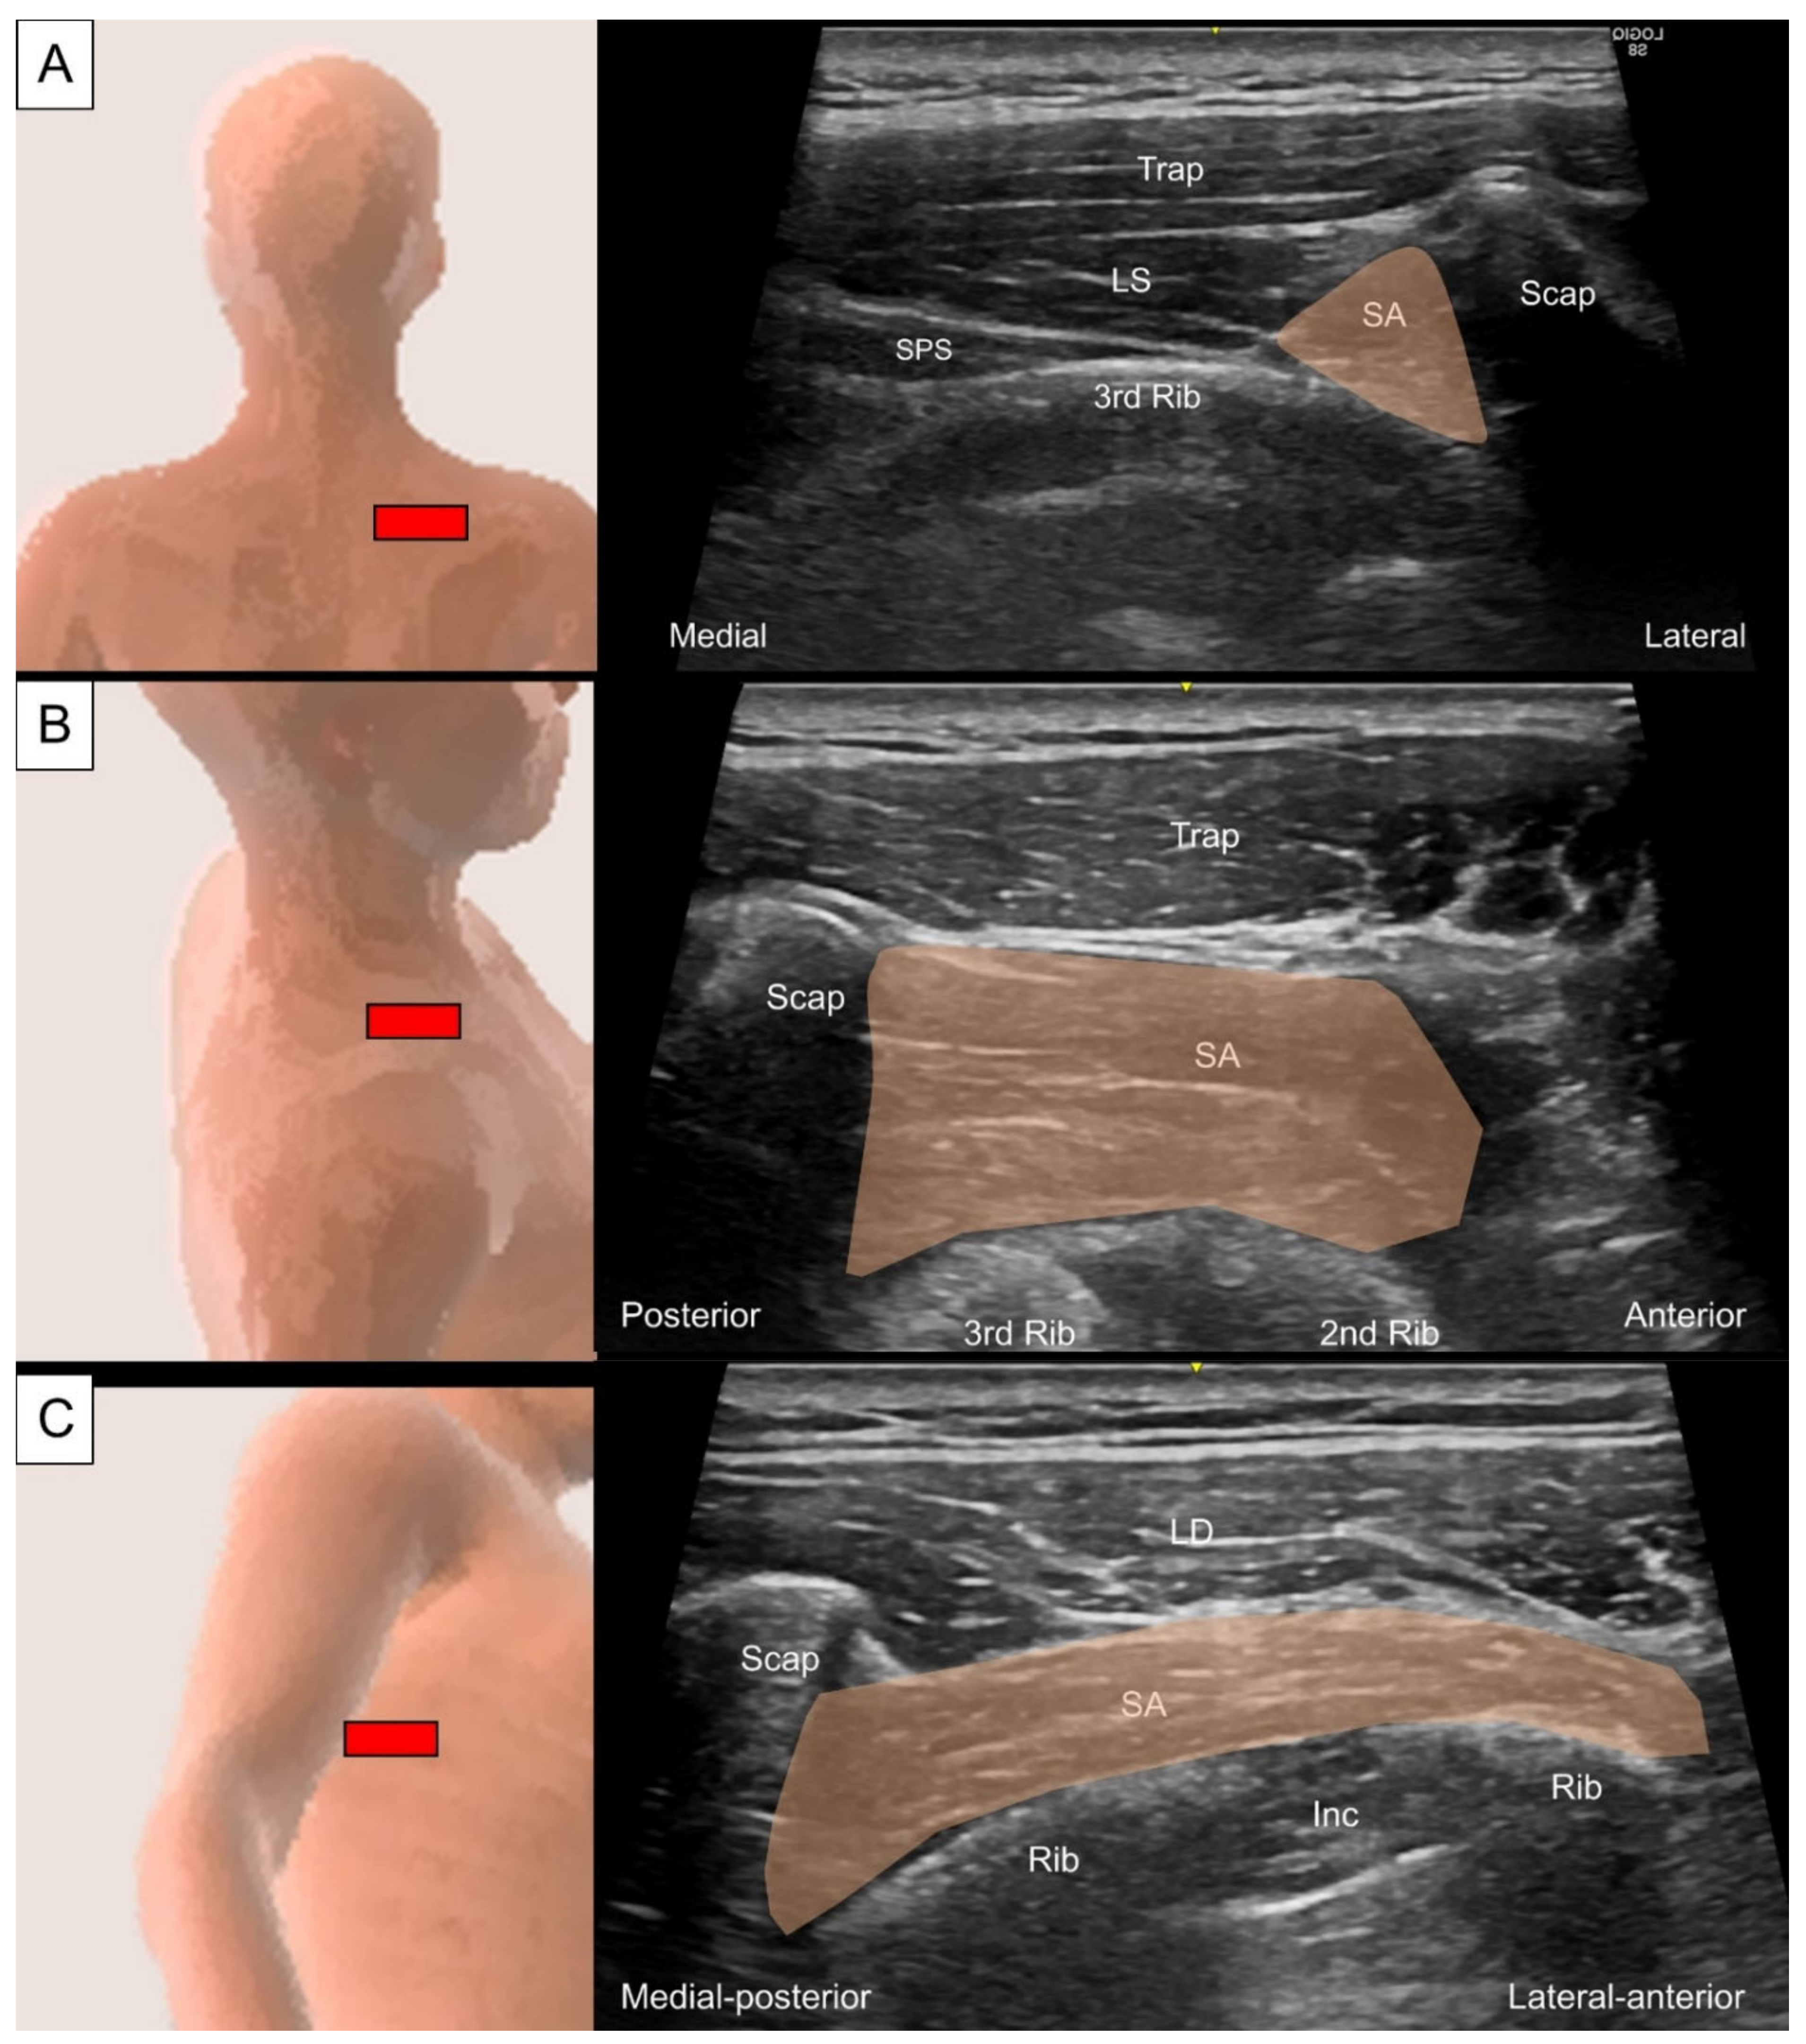

6.2. Serratus Anterior

6.2.1. Anatomy

6.2.2. Sonographic Scanning

6.2.3. Clinical Relevance